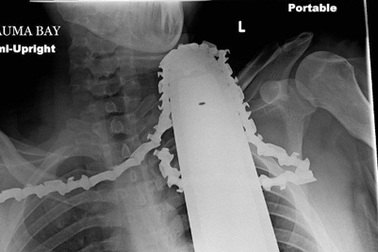

Thoát chết sau khi lưỡi cưa máy cắm sâu vào cổĐộng cơ được tháo khỏi máy cưa nhưng lưỡi cưa vẫn được để nguyên ở cổ để đề phòng mất máu.